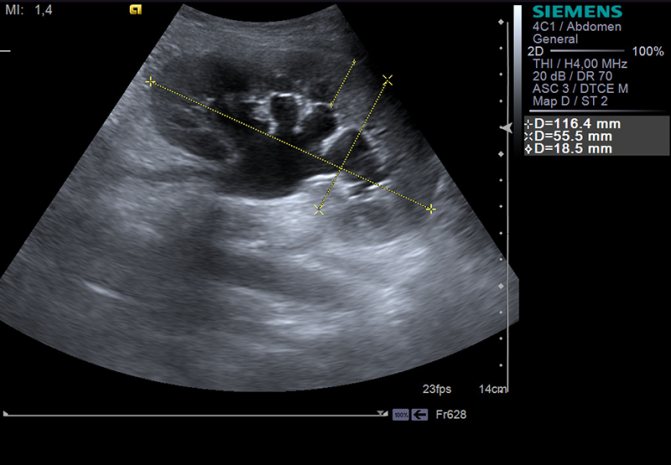

Схожесть симптомов нефрита с признаками гриппа и ОРВИ заставляет специалистов прибегнуть к методам дифференцированной диагностики. Подтвердить предположение врачей по поводу воспаления в области почек могут следующие способы диагностики нефрита:

- УЗИ почек с эффектом контрастной подсветки (допплерометрии);